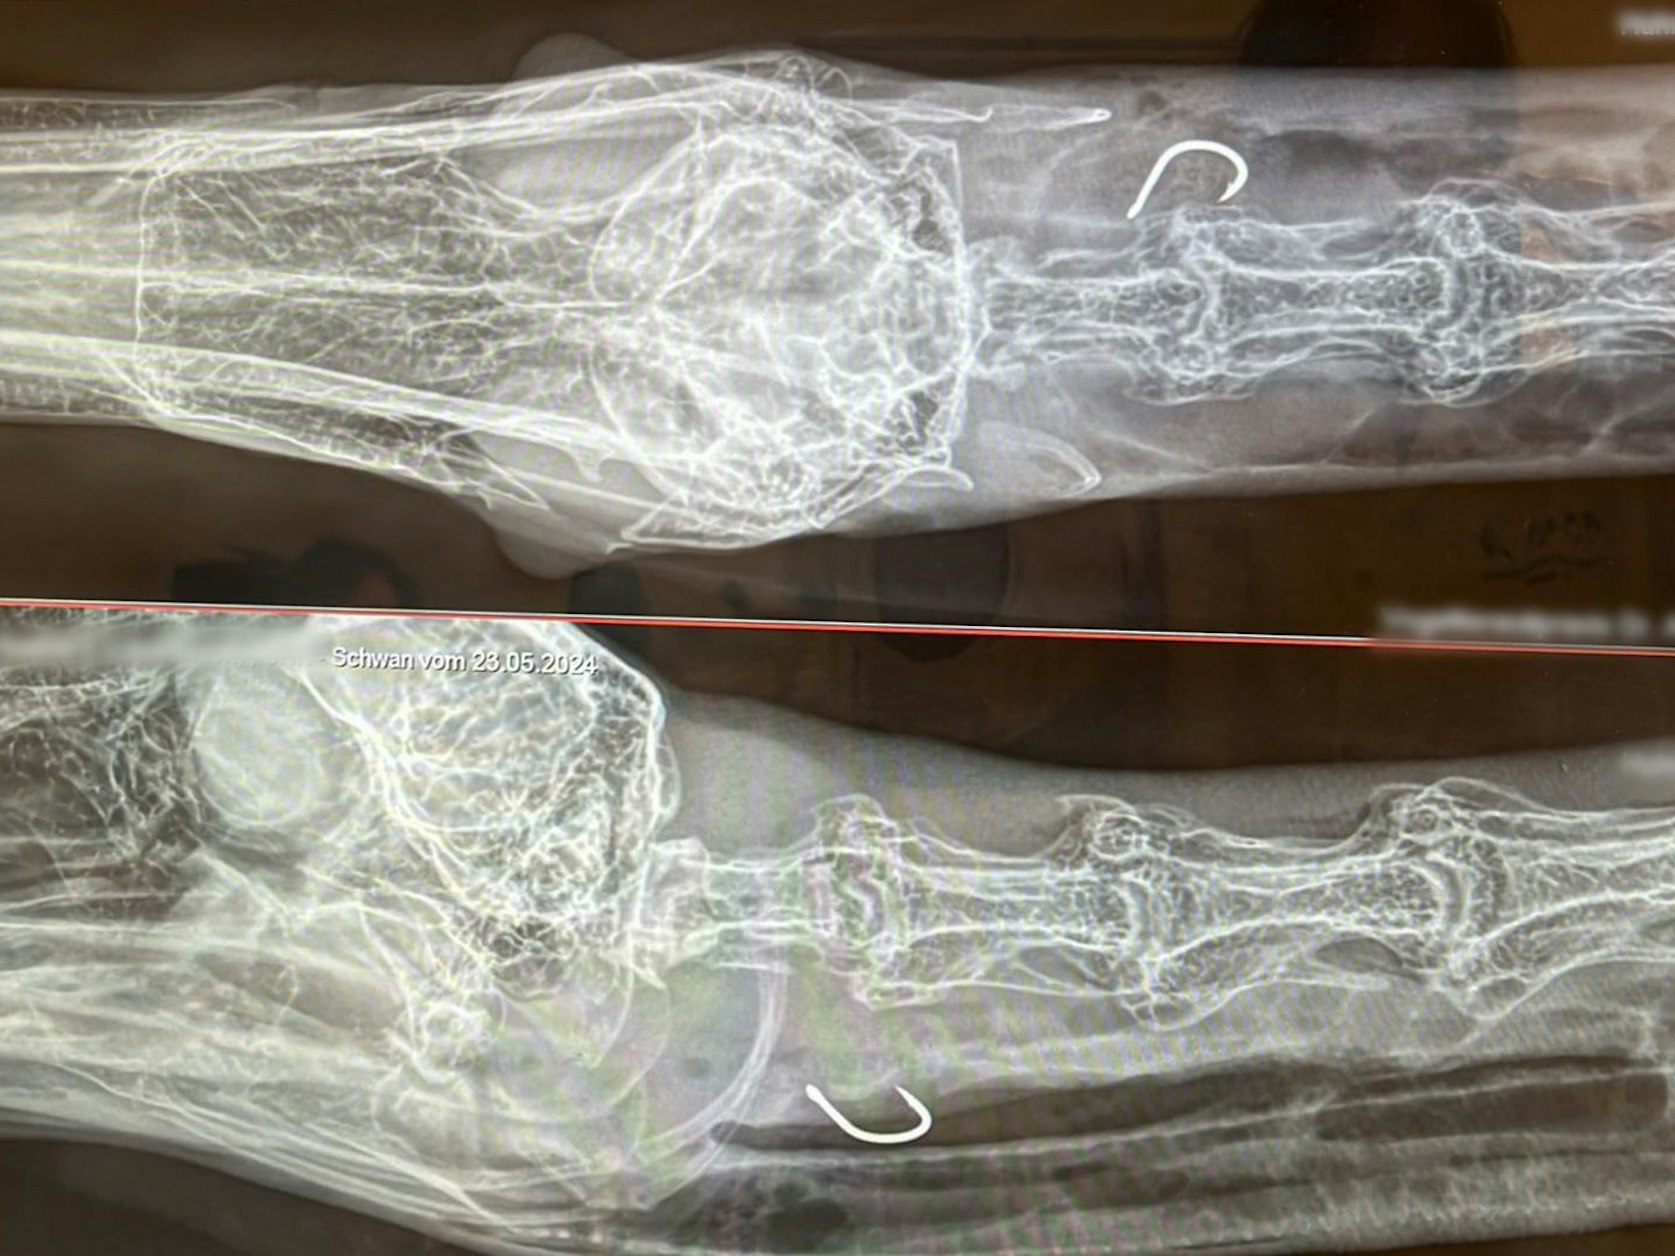

Auf den Röntgenbildern ist der Angelhaken im Hals des Schwans zu sehen, den er am Mittwoch (22. Mai 2024) am Adenauer Weiher in Köln verschluckt hat.